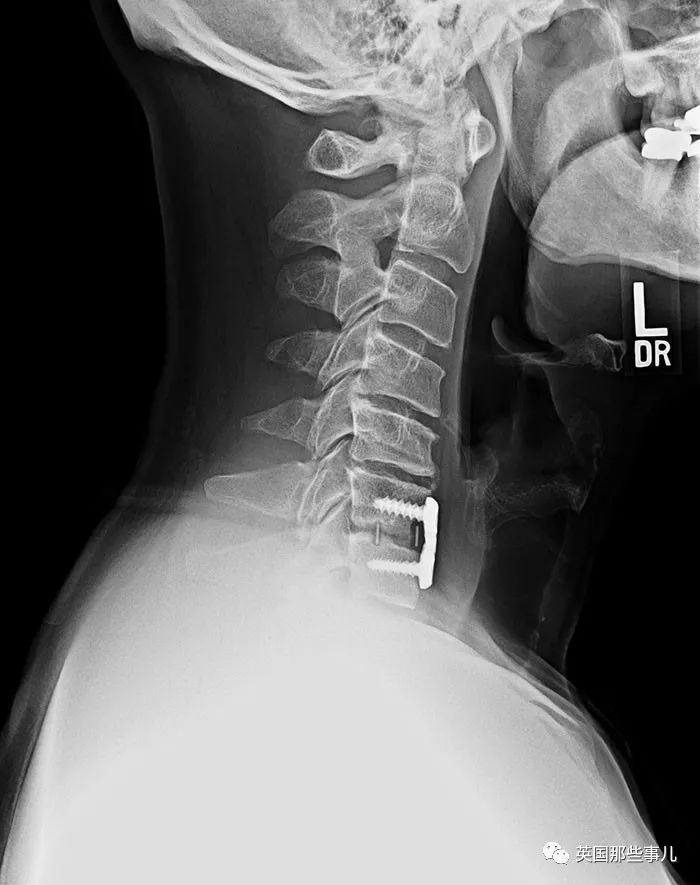

醫生在我爸爸的脖子裏植入了一個(ge) 裝置,裏麵含有未發育的骨細胞和幹細胞,用來幫助他的部分脊椎再生,科學真是太偉(wei) 大了。